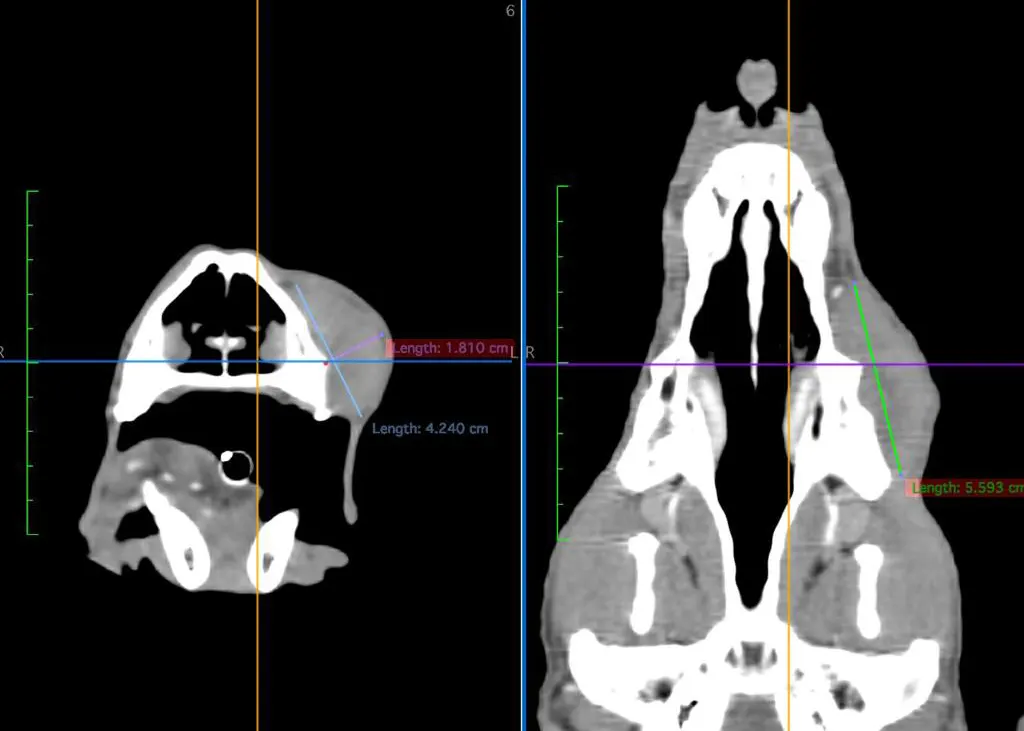

La tomografía veterinaria es un método de imagen avanzado y no invasivo que revoluciona el diagnóstico veterinario. En COV Guadalajara, contamos con un equipo de última generación multi corte General Electric Light Speed Plus

Cortes transversales multidireccionales y reconstrucciones 3D para analizar tumores, fracturas o malformaciones sin superposición de imágenes.

Identifica lesiones ocultas en estudios tradicionales (metástasis, microhemorragias) y distingue con claridad tejidos sanos vs. afectados.

Mapas anatómicos precisos para cirugías y radioterapia, reduciendo riesgos y mejorando los resultados clínicos.

La diferencia de la tomografía sobre los estudios tradicionales es que nos permite observar el cuerpo en distintos cortes transversales, evitando la superposición de estructuras, lo que permite generar imágenes con mejor resolución. También permite detectar diferencias entre densidades tisulares más pequeñas que los estudios convencionales, generando imágenes con mayor resolución de contraste, permitiéndonos diferenciar distintas estructuras de tejidos blandos.